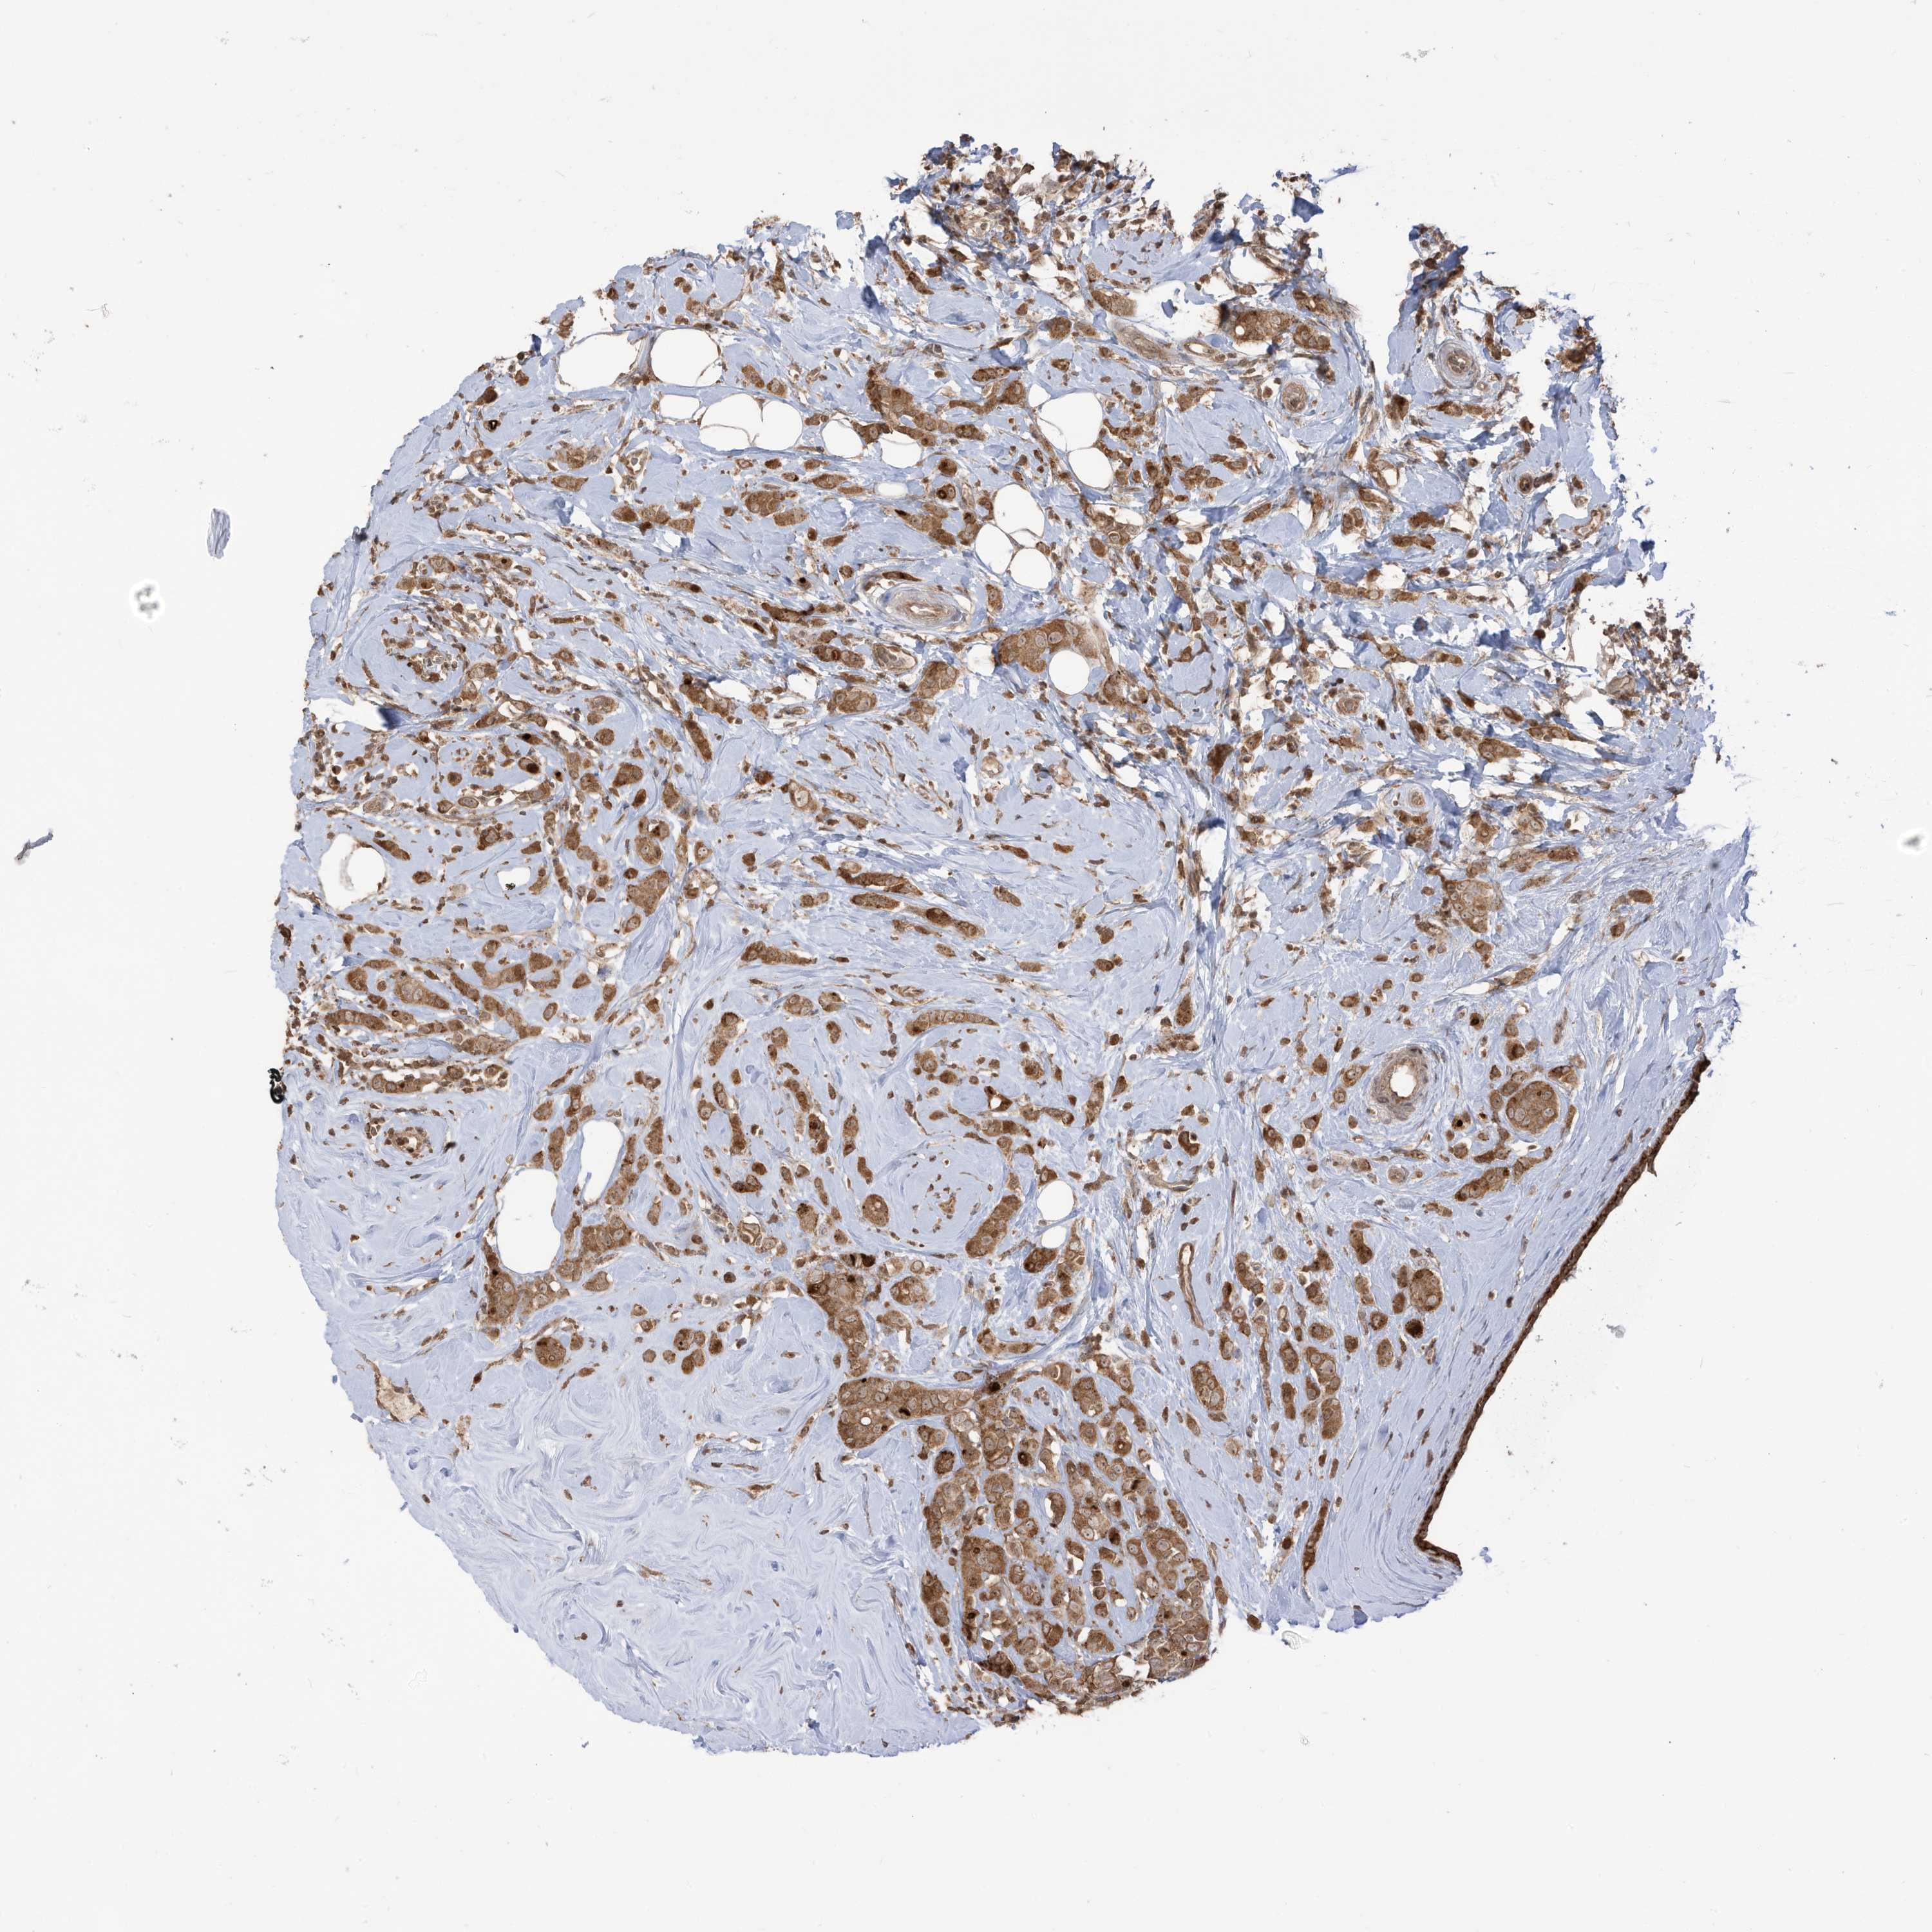

BRCA TCGA BRCA VALIDATION PROTEIN EXPRESSION

Breast cancer

Human cancer